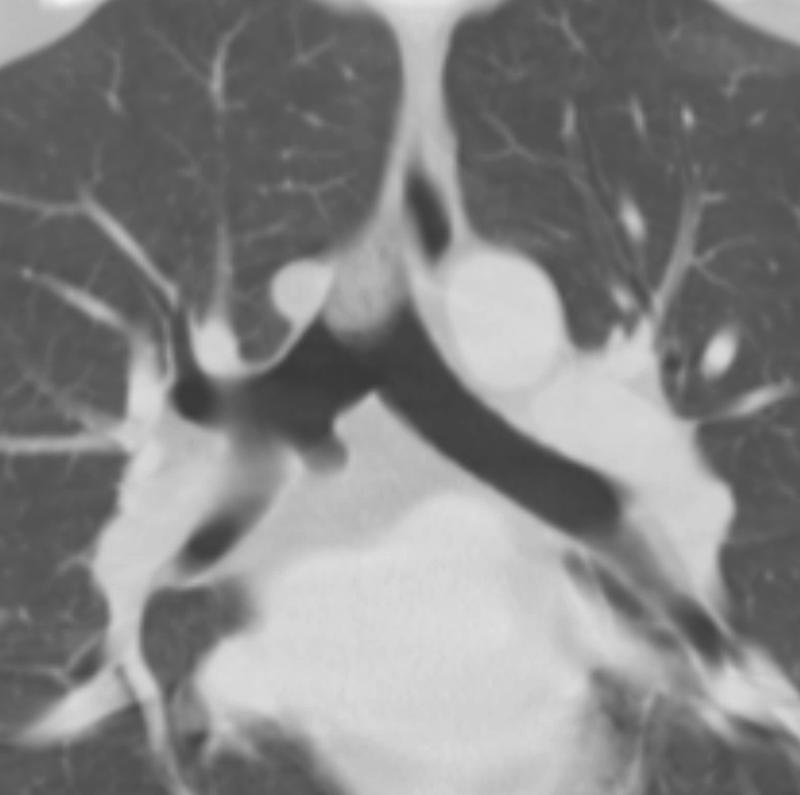

Gallery Congenital cardiac bronchus - and plug

cardiac bronchus - and plug